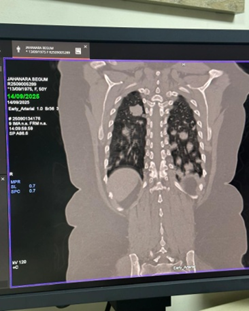

Case Presentation: A 50-year-old female presented with anorexia and cervical lymphadenopathy came for evaluation and management. Chest radiograph and CT scan demonstrated multiple bilateral pulmonary nodules without abdominal organ involvement. Core biopsy of a pulmonary lesion confirmed the diagnosis of NHL, B-cell type.

• Chest radiograph revealed multiple nodular opacities in both lung fields.

• CT chest demonstrated numerous, variable-sized nodules scattered throughout both lungs, with no mediastinal mass, pleural effusion, or consolidation.

Given the radiological appearance, the differential diagnosis included pulmonary lymphoma versus metastatic disease.